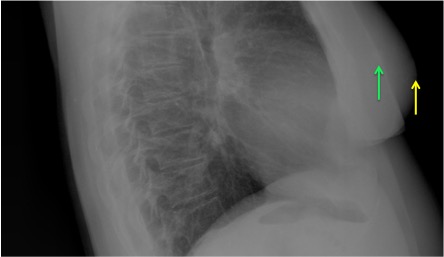

CASO: Operada de cáncer de mama izquierda en revisión.

Hallazgos:

- Prótesis mamaria izquierda (obsevar el aumento de densidad homogéneo y de bordes bien definidos en la placa PA y lateral)

- Parénquimas pulmonares y silueta cardiomediastínica sin alteraciones significativas.